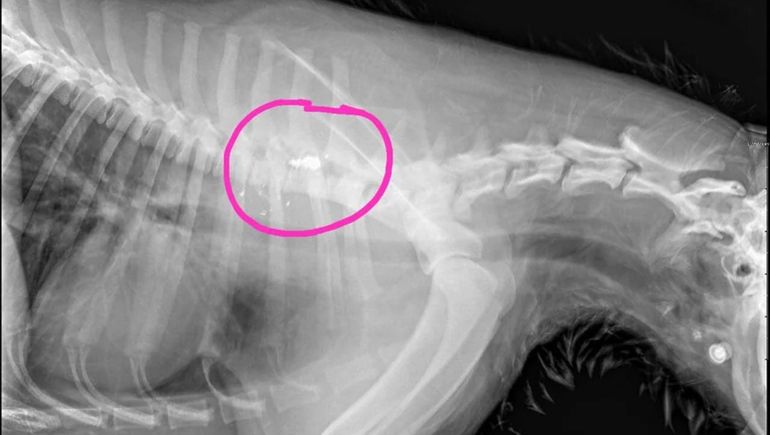

“Pudieron detectar que había una bala alojada en una de sus vértebras, así que esto es producto de un tiro que ha recibido”, explicó el rescatista.

El proyectil, que se ve perfectamente en las radiografías que le realizaron al perro, le provocó una lesión neurológica grave que le impide caminar.